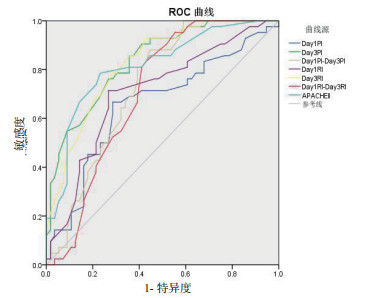

第1天PI、第3天PI、Day1PI-Day3PI、第1天RI、第3天RI及Day1RI-Day3RI、APACHE Ⅱ预测脓毒症患者预后的AUC分别为0.657(95%CI:0.545~0.769)、0.835(95%CI:0.758~0.913)、0.730(95%CI:0.631~0.828)、0.707(95%CI:0.602~0.812)、0.826(95%CI:0.746~0.906)、0.705(95%CI:0.602~0.808)、0.815(95%CI:0.728~0.901),P均<0.01,可见第3天PI及RI的预测价值最大与APACHE Ⅱ相当,而第1天PI、Day1PI-Day3PI、第3天RI及Day1RI-Day3RI的预测价值降低。当第3天PI截断值为1.02时,预测脓毒症预后的灵敏度为85.7%、特异度为61.3%,第3天RI截断值为0.62时,预后脓毒症预后的灵敏度为78.6%、特异度为71.4%。见图 6及表 5。

|

| 图 6 各指标预测预后的ROC曲线 Fig 6 ROC curve of indexes for predicting prognosis |

脓毒症患者第1天PI > 1.3,可预测患者出现谵妄的可能,AUC为0.908,敏感度为95%,特异度为88%。艾美林等[16]的研究表明第1天PI、RI均可预测SAE,AUC均 > 0.7,截断值分别为1.16、0.65。SAE又是脓毒症患者死亡的独立危险因素,且本研究显示PI及RI能反映疾病严重度及脑功能情况,动态PI、RI可反映病情变化,因而认为动态TCD检测对脓毒症预后有一定的预测价值。APACHE Ⅱ是目前我国重症病房广泛应用的评价危重患者病情严重程度的评分系统。在本研究中第1天PI、第3天PI、Day1PI-Day3PI、第1天RI、第3天RI、Day1RI-Day3RI及APACHEⅡ均可预测脓毒症患者预后,AUC分别为0.657、0.835、0.730、0.707、0.826、0.705、0.815,其中第3天PI及RI预测价值较大,与APACHE Ⅱ相当,当第3天PI截断值为1.02时,灵敏度为85.7%、特异度为61.3%,第3天RI截断值为0.62时,灵敏度为78.6%、特异度为71.4%。PI、RI前后变化值预测预后的价值不高,但Day1PI-Day3PI、Day1RI-Day3RI截断值分别为0.13、0.38时有较高的特异度,特异度为88.1%、83.3%,灵敏度为55.4%、57.1%。